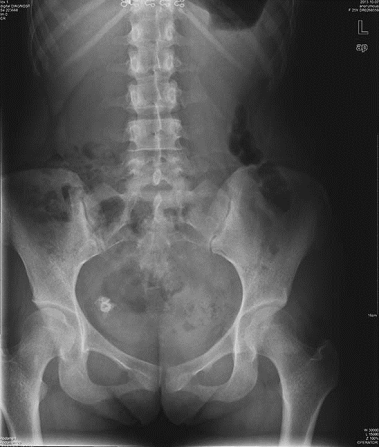

卵巢畸胎瘤腹中X线 摄片卵巢恶性肿瘤MR检查

盆腔右侧见一大小为1.7×1.5cm不均匀 盆腔右侧子宫前方不规划囊实性混杂性号影,有 高密度钙化影,边界尚清 分隔及软组织成份,增强扫描实性结节呈中强度改变